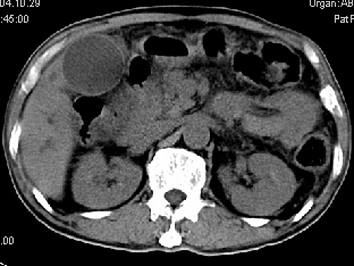

问题 男,58岁,患者右季肋区疼痛,皮肤黄染,可触及肿大胆囊,B超提示胆囊颈部肿块影,CT所见如图,最可能的诊断是 ( )

选项 A、慢性胆囊炎 B、胆囊腺肌增生症 C、胆囊癌 D、胆囊黄色肉芽肿 E、胆囊息肉

答案 C